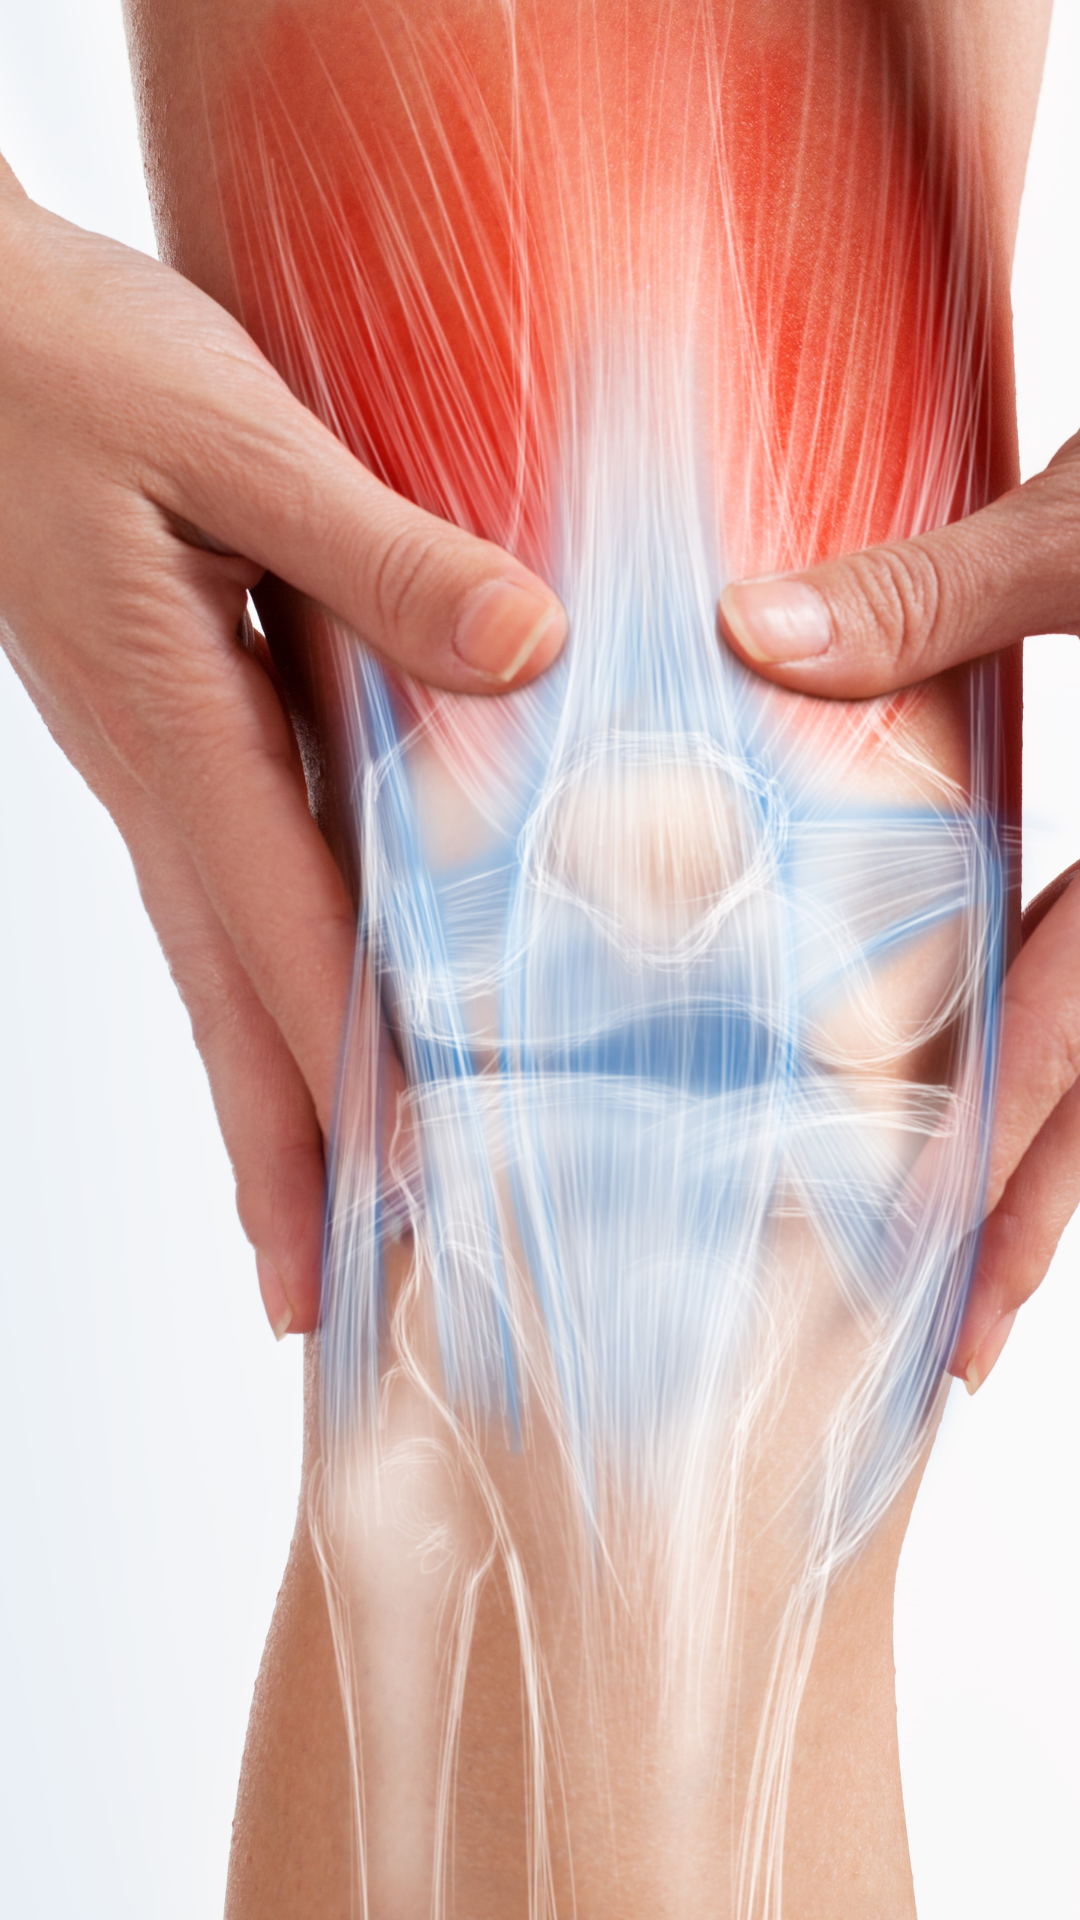

La artroscopia permite diagnosticar y tratar problemas como:

Beneficios:

En CIFO te ayudaremos a decidir la opción que te ayudará a moverte libremente. Nuestra prioridad es que no detengas

tu actividad y vivas la vida con plenitud. ¡Al 100%!